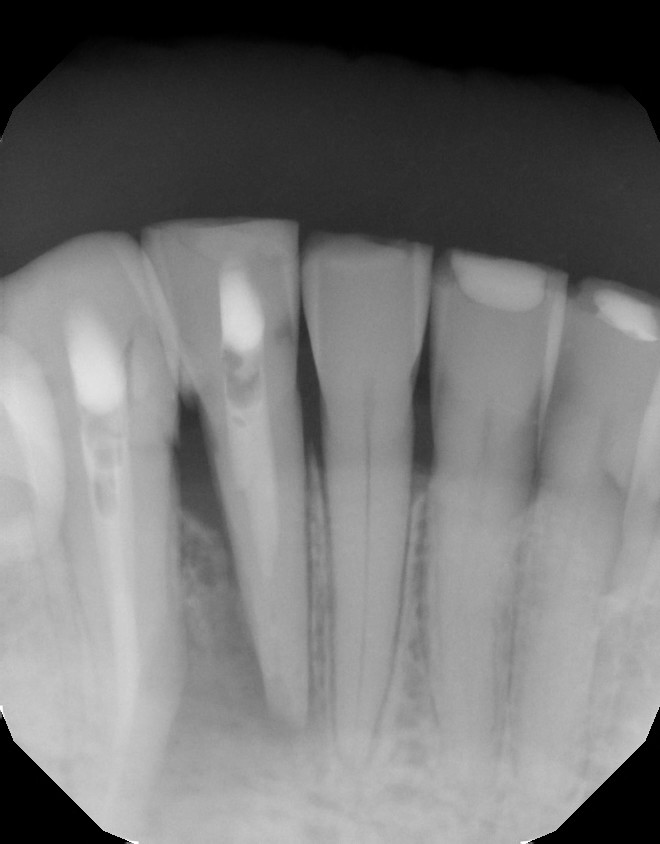

| CBCT shows the apical and lateral bone loss on #26 and #27. The lateral bone loss on #27 is also suggestive of a possible root fracture, but since the tooth is necrotic, radiographic appearance alone is not enough evidence to diagnose this with a root fracture. CBCT also shows a 2 canaled root form on #26. |

| After 6 months of CaOH therapy we saw significant bone healing. The canals were obturated and case completed. |